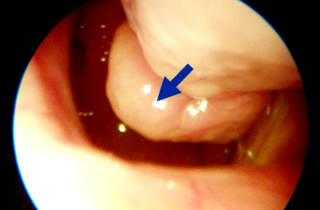

Основным и наиболее эффективным методом исследования является эндоскопия. Она позволяет точно определить степень и местонахождение патологии.

При ринодиагностике отмечается гиперплазия (утолщение) оболочки носа нижнего отдела, реже – среднего. Поверхность измененных участков бывает от гладкой до бугристой. Слизистая покрасневшая и несколько синюшная. Увеличения носовых раковин при утолщении костной основы не происходит.